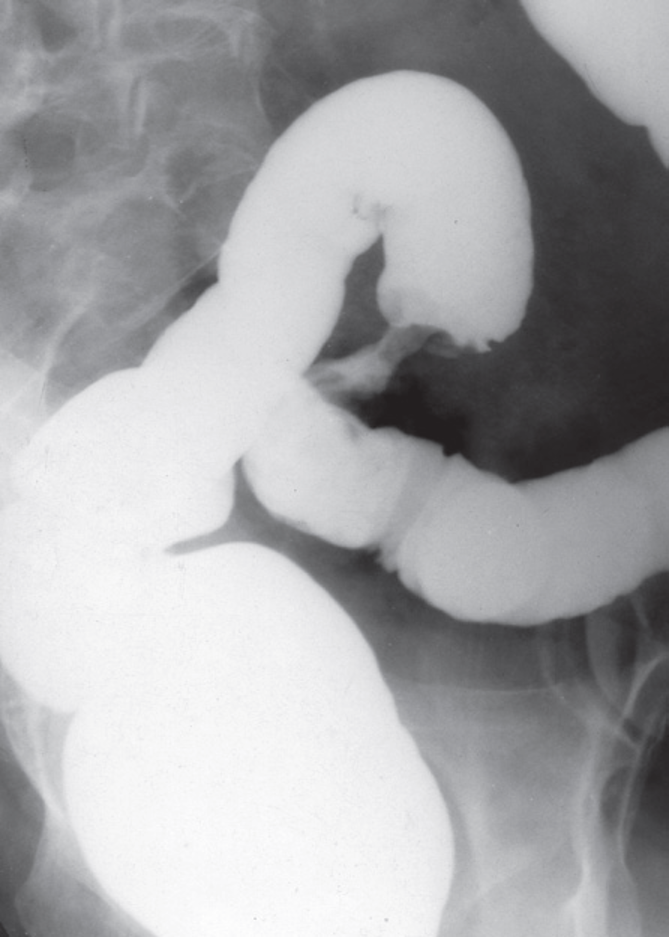

Stricture : Barium enema showing a short, circumferential narrowing in the sigmoid colon from a carcinoma.